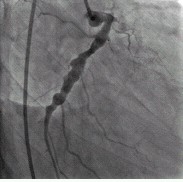

例2,男,40岁,以阵发性胸闷三年,加重一月入院。查体:心界扩大,心率74次/分,心尖区可闻及Ⅲ级收缩期杂音。心电图:V1~V4导联呈QS型,ST段抬高。冠状动脉造影示:LCX、RCA弥漫扩张,前向血流TIMIⅢ级;LAD开口100%闭塞。(图3,图4)。IVUS示:LCX、RCA显著扩张,未见明显动脉粥样硬化斑块。心脏彩超示:左心室前壁节段性运动减弱,心尖段室壁瘤形成;左心房内径39mm,左心室舒张末期前后径70mm;二尖瓣轻度关闭不全,三尖瓣轻度关闭不全;EF:41%。行冠状动脉搭桥手术(CABG)及室壁瘤切除术,术后随访4个月,无胸闷症状发生。

图4:例2冠状动脉造影显示右冠状动脉显著扩张